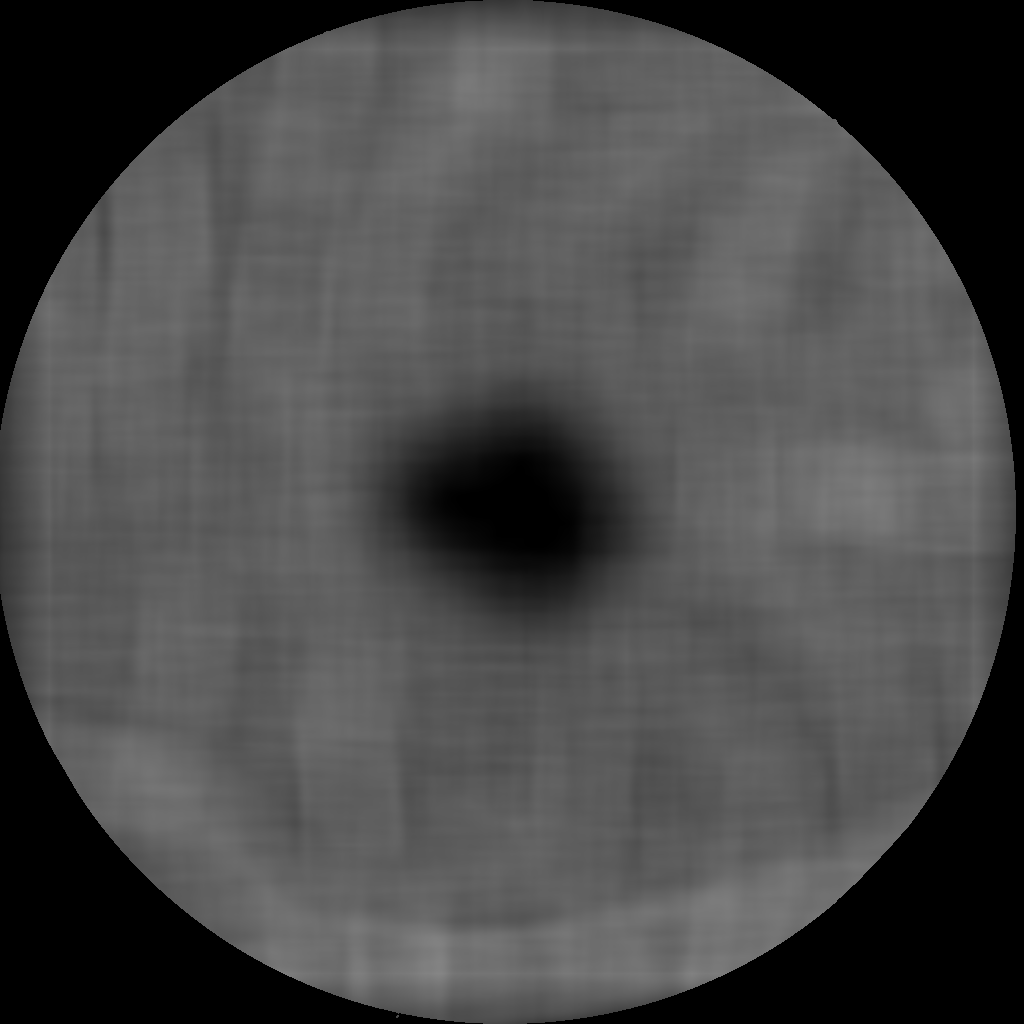

Refer to caption

(a) Smoothed Gabor representation

(b) Piecewise constant image

Figure 3: Image representations for the FAZ identification

where u:Ωr:𝑢Ωsuperscript𝑟u:\Omega\rightarrow\mathbb{R}^{r} denotes a bounded piecewise constant function and u0\lVert\nabla u\lVert_{0} the total boundary length of its partitioning, cf. [20, 8, 24] for details. The second term provides approximation to the original data and the first term enforces the partitioning, where the parameter γ𝛾\gamma controls the balance between the two penalties. We use the fast strategy and code presented in [24] for solving a discretization of (3) to receive the piecewise constant image representation, see Figure 3(b). The FAZ is then identified by choosing the darkest segment in the central part of the image.